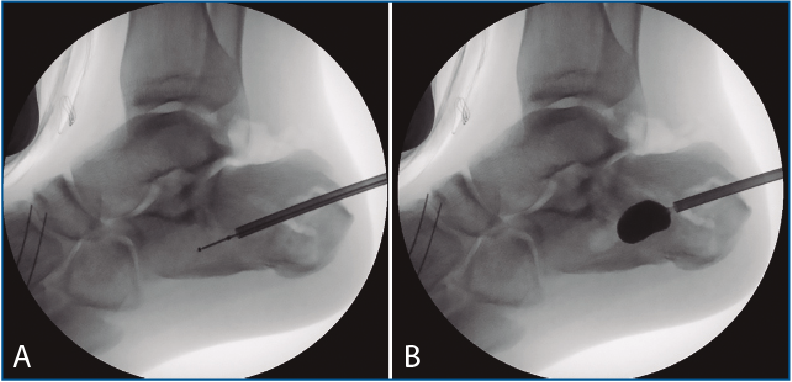

Figura 4. A: control de escopia intraoperatoria (perfil) de la lesión reducida con ayuda de periostotomos; B: control de escopia intraoperatoria (perfil) tras insertar la primera aguja mientras se mantiene la reducción con un periostotomo; C: control de escopia intraoperatoria (axial de calcáneo) tras insertar la primera aguja mientras se mantiene la reducción con un periostotomo; D: control de escopia intraoperatoria (axial de calcáneo) tras colocación del primer tornillo de osteosíntesis.

Figura 5. A: control de escopia intraoperatoria (perfil) de la localización óptima para insuflar el balón de calcaneoplastia; B: control de escopia intraoperatoria (perfil) tras la insuflación del balón de calcaneoplastia.